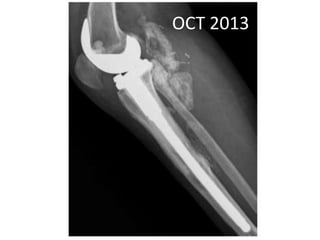

OCT 2013

• Pain around knee joint diminished

• Further resection ??

• Patient refused

• Clinical improvement persisted until jan 14

• MAY 2013 •DENOSUMAB started • 360 mg subcutaneous dose • Followed by 120 mg every month

• Pain aroundknee joint diminished • Further resection ?? • Patient refused • Clinical improvement persisted until jan 14 • Presented with Rapidly growing painful palpable mass • Open biopsy : high grade sarcoma • A/K amputation